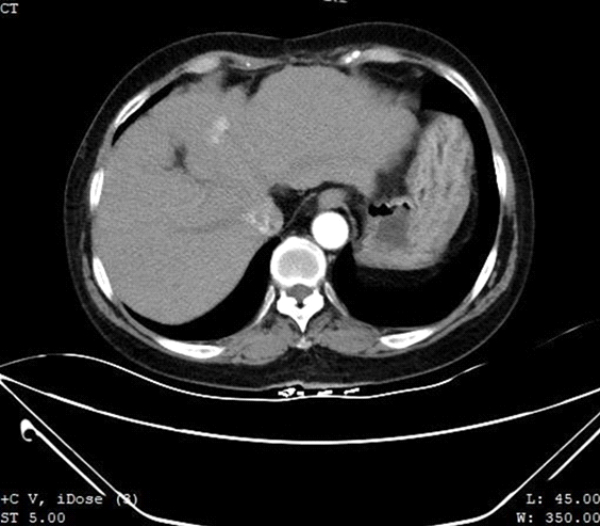

64-letnia kobieta od ponad 30 lat cierpi na zapalenie w?troby typu B, sze?? lat wcze?niej przeby?a cz??ciow? hepatektomi? segmentu VII i splenektomi? z powodu pierwotnego raka w?trobowokomórkowego. Na nasz oddzia? trafi?a po badaniu MRI wykonanym w naszym szpitalu trzy miesi?ce wcze?niej, które wskazywa?o na marsko?? w?troby i podejrzenie z?o?liwych guzków w segmencie IV w?troby. Ponowne badanie wykonane metod? TK z kontrastem wykaza?o nieznacznie hipodensyjne ognisko o ?rednicy oko?o 1,5 cm w segmencie IV lewego p?ata w?troby (Ryc. 1) z wyra?nym nierównym wzmocnieniem w fazie t?tniczej i wrotnej oraz nieznacznym wyp?ukiwaniem w fazie ?ylnej, które podejrzewano o nawrót raka w?trobowokomórkowego.